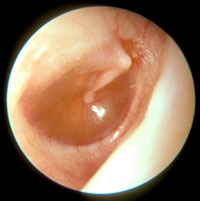

Normal Tympanic Membrane

TM is translucent

Handle of the malleus is vertical

No erythema